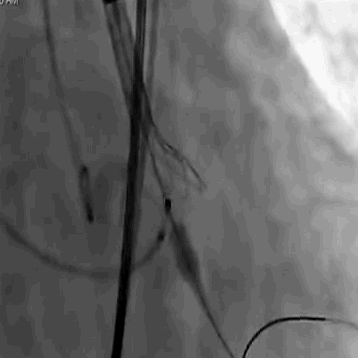

手术采用22 mm TaurusAtlas球囊进行预扩,植入AV23TaurusNXT主动脉瓣。第一次释放后位置偏高,瓣膜完全回收。第二次释放到工作位,检测左右冠血流灌注情况,考虑左瓣叶的瓣尖钙化影响左冠脉血流,使用第二次回收后,预置LCA保护。之后再次释放瓣膜至工作位,在GuidezillaII支撑保护下送 4.0×18mm 支架至 LAD 近段,之后瓣膜精准释放,后用22mm TaurusAtlas球囊后扩。术后即刻经胸超声心动图评估显示少量瓣周漏,平均跨瓣压差为10mmHg,主动脉瓣口峰值流速为2.3m/s,有效瓣口面积为1.80cm²,血流动力学指标理想。

术中影像

主动脉根部造影可见重度钙化

22mm球囊预扩

瓣膜第一次释放

未达到最佳位置,完全回收

重心定位后,第二次释放到瓣膜工作位,发现LCA灌注缝隙狭小

预置LCA保护

完全回收,第三次定位释放,瓣膜位置良好

瓣膜工作位释放“烟囱支架”

瓣膜完全释放后22mm球囊后扩

释放后造影